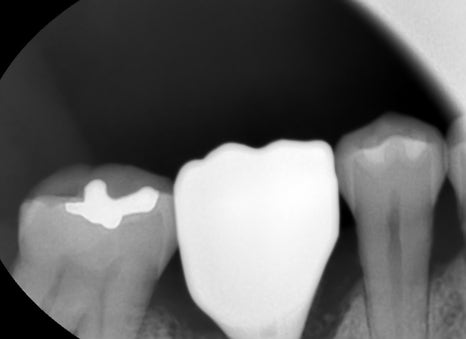

임플란트 시술시에는 환자의 전신병력도 굉장히 중요하기에 전신병력을 고려하여 3차원 CT촬영을 통하여 치조골의 양 또는 골폭 그리고

식립하는 위치를 확인하는 정밀진단이 필요하기에 3차원 CT촬영 후 임플란트 수술을 진행하고 있습니다.

임플란트 픽스쳐가 이식이 삐뚫지 않아야 오래 사용 할 수 있습니다. 위 사진과 같이 뼈가 부족할 시에는 임플란트를 식립 후 뼈이식을 동시에 하는 경우도 생깁니다.